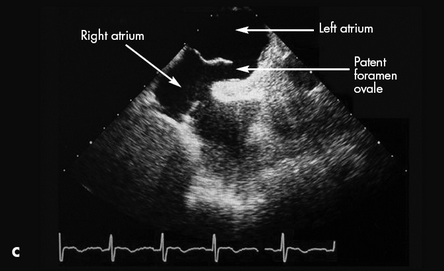

CT scans showed both a pulmonary embolus (A) and a thrombus in the wall of the abdominal aorta (B). Anticoagulation therapy was initiated. A Doppler study showed a left lower extremity deep venous thrombus. Further evaluation with transesophageal echocardiography showed a patent foramen ovale (C) and an interatrial aneurysm, with a positive bubble study.* The patient had no known history of either condition. Because of the patent foramen ovale, thrombi had traveled not only to the lungs but also to the aorta. This likely caused the spinal ischemia and paraparesis.